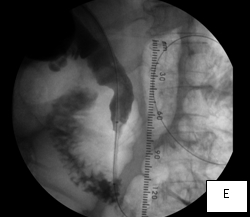

In this woman, crossing her obstructed ampulla of Vater at ERCP failed, so I had to percutaneously deploy a biliary drainage catheter across it while waiting for the result of her biliary brushings. The single image illustrates the deployed catheter across the obstruction.